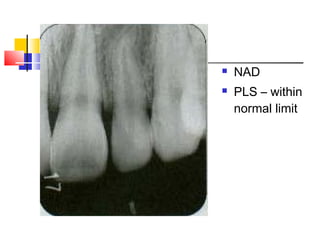

Example Cases – Case 1

 A 14-year-

old boy fell

and hit his

teeth #21 &

22. Slight

bleeding

and mobility

was

observed.

 NAD

 PLS – within

normal limit

 One month

later,

discoloration

is noted.

 The

diagnosis is

subluxation

resulting in

disruption

of the blood

supply to

the pulp.